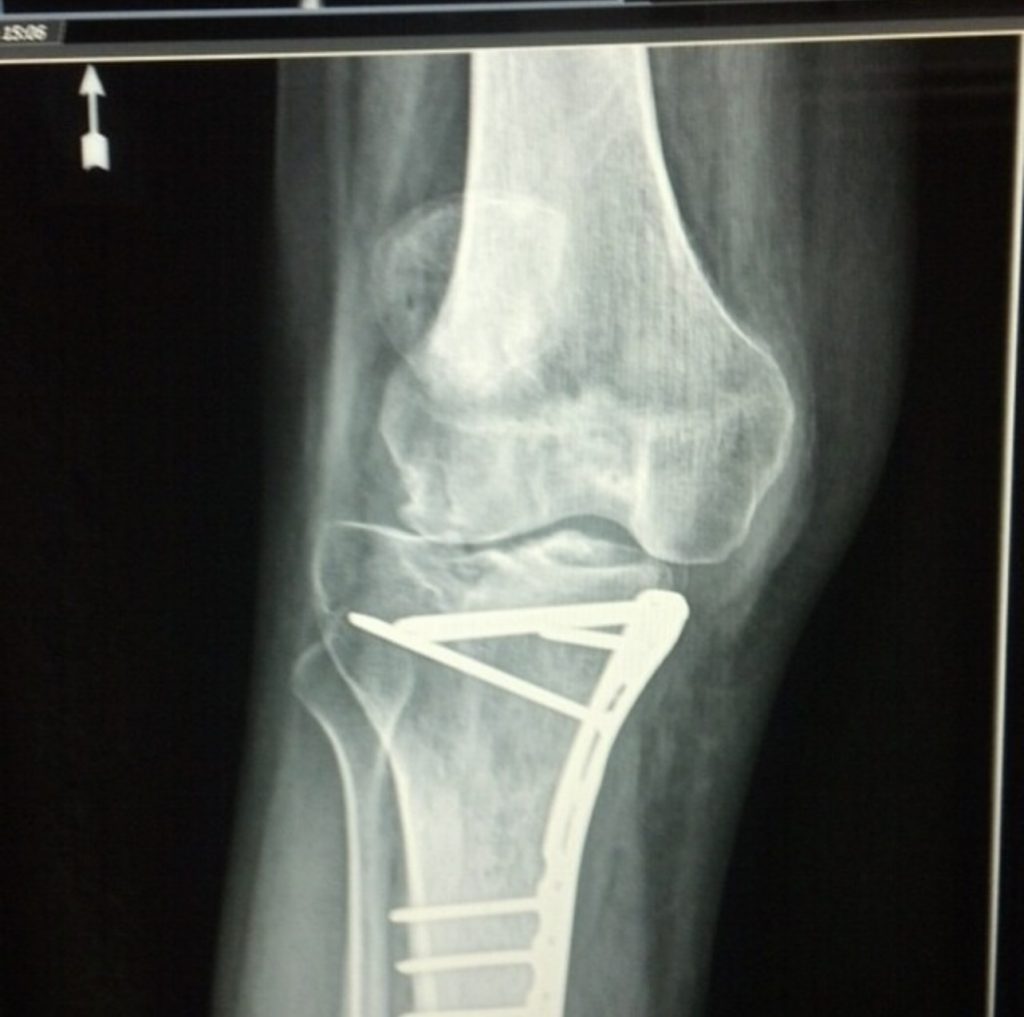

In June 2014, I was involved in a skateboarding accident in which I suffered a tibial plateau fracture and tore almost all the ligaments and meniscus in my right knee. The pain was surreal, and I was completely unable to walk or bear any weight on it. I immediately underwent four separate knee surgeries (each requiring physical therapy) over the course of the next year in my state capital of Columbia, South Carolina. After the fourth and final surgery and physical therapy was completed, I was hoping to hear good news from my doctors about my ability to walk again. Instead, I was presented with the impossible choice of either amputation of my leg above the knee or fusion of my tibia and femur at the knee joint as my only two options going forward because they were unable to do anything more for me.

I was not pleased with this outcome at all and immediately began seeking a second opinion. With the help of my father, we scoured the country for orthopedic surgeons who were up to the task of fixing my knee. After speaking with several who turned me away, we finally found Dr. Rozbruch at HSS and I will be forever grateful that we did. From our first meeting, I knew that Dr. Rozbruch would be the doctor that could help me walk again. He is very personable and friendly and leaves you with the impression that you are more than just another case for him to diagnose and manage. He answered all my questions, questions that my doctors in South Carolina were unable to answer. He gave me hope during what had been the worst year of my life. After agreeing to work on my knee, I ended up having four more knee surgeries with Dr. Rozbruch at HSS. That’s eight total surgeries if you’ve been keeping track! One of the surgeries involved the use of an Ilizarov frame. It consisted of two rings around my leg/knee each connected by pistons that could be adjusted using a special tool.

Over the course of about 6 months, I followed specific daily directions for adjusting the frame. It was painful at times, but I could tell that it was slowly correcting my misaligned tibia. When the frame was finally removed, I could tell a huge difference in the way my leg looked and how the bones were set. Physical therapy was easier than ever before, and I was finally able to make some progress toward walking again. There was a light at the end of a very dark tunnel.